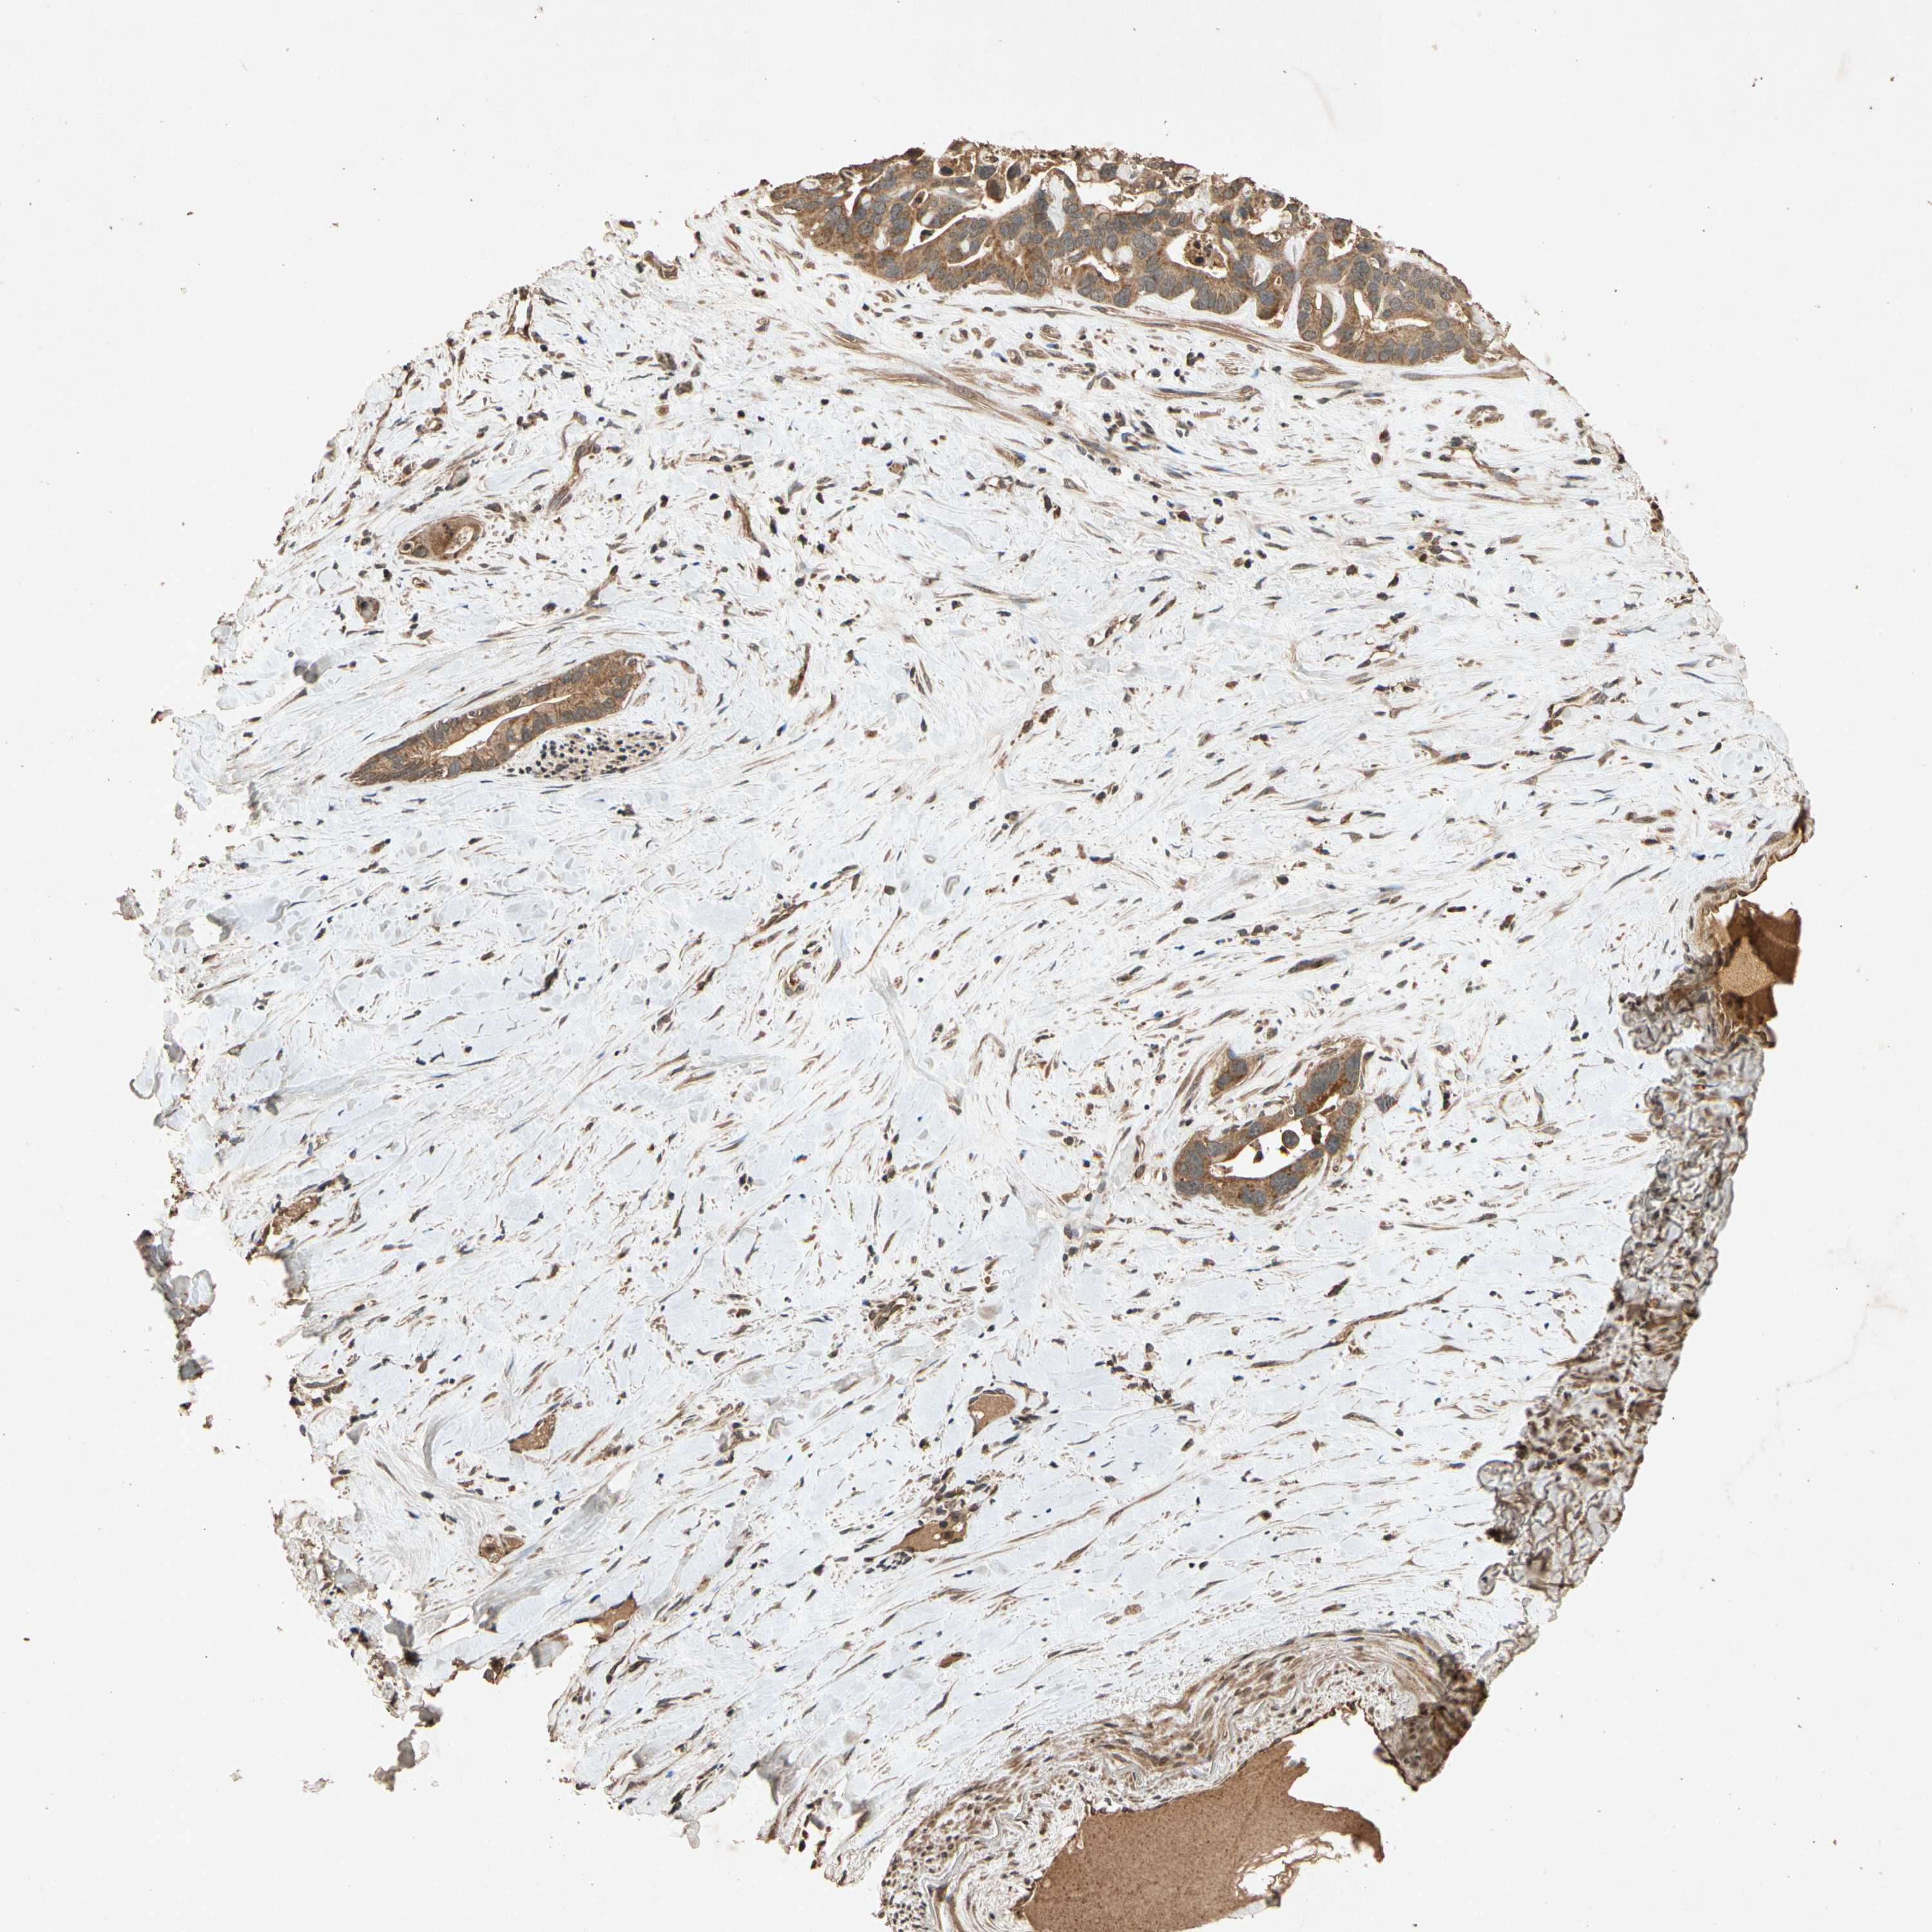

LIVER CANCER - Protein expressioni

A mouse-over function shows sample information and annotation data. Click on an image to view it in a full screen mode. Samples can be filtered based on level of antibody staining by selecting one or several of the following categories: high, medium, low and not detected. The assay and annotation is described here.

Note that samples used for immunohistochemistry by the Human Protein Atlas do not correspond to samples in the TCGA dataset.

Antibody stainingi

Antibody staining in the annotated cell types in the current human tissue is reported as not detected, low, medium, or high, based on conventional immunohistochemistry profiling in selected tissues. This score is based on the combination of the staining intensity and fraction of stained cells.

Each image is clickable and will lead to virtual microscopy that enables deeper exploration of all samples and also displays staining intensity scores, fraction scores and subcellular localization as well as patient and tissue information for each sample.

Antibody HPA000994

Antibody CAB008681

Staining

High

Medium

Low

Not detected

Intensity

Strong

Moderate

Weak

Negative

Quantity

>75%

75%-25%

<25%

None

Location

Nuclear

Cytoplasmic/membranous

Cytoplasmic/membranous,nuclear

Carcinoma, Hepatocellular, NOS

Cholangiocarcinoma